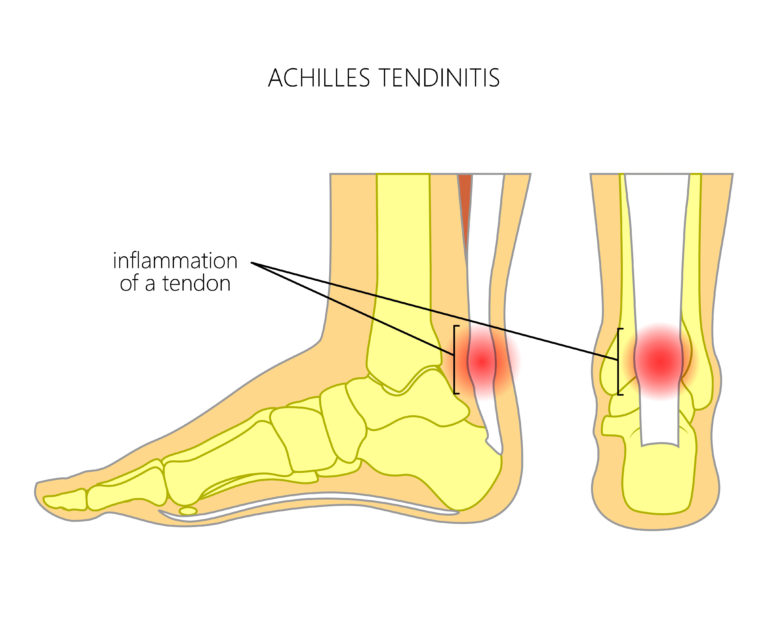

Achilles tendinitis – Mayo Clinic

Inflammation Of Achilles Tendon Cheapest Dealers, Save 65% | jlcatj.gob.mx

Achilles Tendonitis Basics | Florida Orthopaedic Institute

Achilles Tendinitis Info | Florida Orthopaedic Institute

Achilles Tendonitis Basics | Florida Orthopaedic Institute

Do You Have Achilles Tendonitis? – Mind & Body Chiropractic

Achilles Tendinitis: Causes, Picture, Symptoms And Treatment

Achilles Tendonitis Causes, Symptoms & Treatment